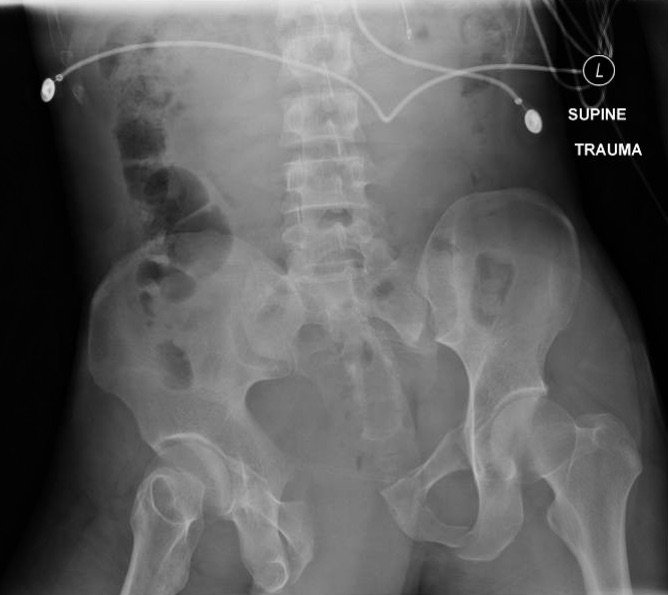

Open Book Pelvic Fracture

A 31-year-old male was brought in by paramedics status post high-speed motorcycle collision. The patient was tachycardic and hypotensive with an initial Glascow coma scale (GCS) of 11. He required immediate blood transfusion and intubation. The patient had multiple traumatic injuries including a deformity to the left thigh and an unstable pelvis. He had palpable distal pulses, and grossly normal sensation and motor function to his bilateral lower extremities.

The initial radiograph of the pelvis shows an open-book pelvic fracture deformity with pubic symphyseal dislocation, left greater than right sacroiliac diastases, and fractures of the left superior and inferior pubic rami, right inferior pubic ramus, and left acetabular anterior column. The additional inlet and outlet radiographs of the pelvis after application of a pelvic binder also show an open book fracture with significant improvement of the widened pubic symphysis.